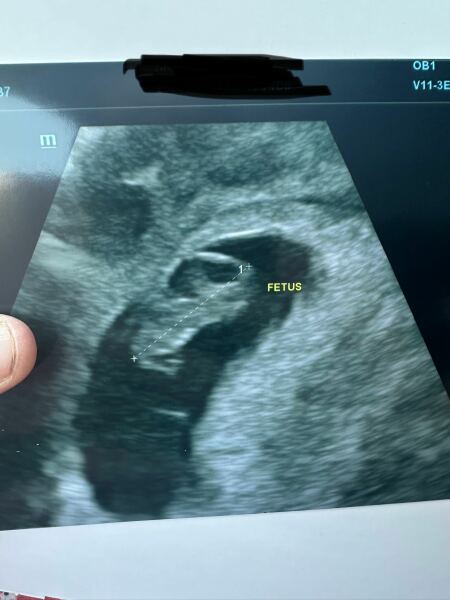

@TheBroonOneAndTheWhiteOne ok thanks lovely. I’m just a bad of nerves. All my scans have been ok so far. I’m currently 8w2d. Had my booking appointment on Sunday. Got another scan next Tuesday. Time is just going so slow 😩. I had some spotting on Thursday so I panicked but private scan was all ok on the Friday. Here’s the photo x

TheBroonOneAndTheWhiteOne · 14/07/2025 21:45

JLucyNick · 14/07/2025 20:55

That's a great scan picture!